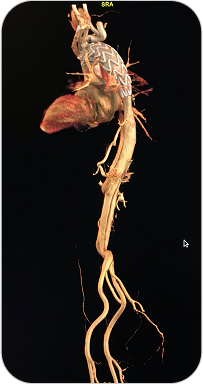

ANGIOTAC

La Angiotomografía es un estudio que utiliza tomografía computada multislice y contraste intravenoso para obtener imágenes detalladas de los vasos sanguíneos. En este caso, permite evaluar de forma precisa la aorta torácica y abdominal, incluyendo sus ramas principales.

La angiotomografía es un estudio especializado para visualizar la aorta y sus ramas principales, detectando enfermedades vasculares con gran precisión.

¿PARA QUE SE UTILIZA?

- Detección y seguimiento de aneurismas de aorta.

Diagnóstico de disección aórtica (emergencia vascular). - Evaluación de estenosis, malformaciones o traumatismos vasculares.

- Estudio previo a cirugías cardiovasculares o colocación de endoprótesis (stent).

- Valoración de arterias renales, mesentéricas y troncos viscerales.

¿POR QUÉ ES UN ESTUDIO DESTACADO?

- Alta resolución y detalle anatómico de la aorta y sus ramas.

Estudio rápido, no invasivo y bien tolerado. - Ideal para urgencias vasculares y planificación quirúrgica.

- Permite reconstrucciones en 3D para mejor visualización por parte del cirujano vascular.

ANGIOTAC

La Angiotomografía es un estudio que utiliza tomografía computada multislice y contraste intravenoso para obtener imágenes detalladas de los vasos sanguíneos. En este caso, permite evaluar de forma precisa la aorta torácica y abdominal, incluyendo sus ramas principales.

La angiotomografía es un estudio especializado para visualizar la aorta y sus ramas principales, detectando enfermedades vasculares con gran precisión.

¿PARA QUE SE UTILIZA?

- Detección y seguimiento de aneurismas de aorta.

Diagnóstico de disección aórtica (emergencia vascular). - Evaluación de estenosis, malformaciones o traumatismos vasculares.

- Estudio previo a cirugías cardiovasculares o colocación de endoprótesis (stent).

- Valoración de arterias renales, mesentéricas y troncos viscerales.

¿POR QUÉ ES UN ESTUDIO DESTACADO?

- Alta resolución y detalle anatómico de la aorta y sus ramas.

Estudio rápido, no invasivo y bien tolerado. - Ideal para urgencias vasculares y planificación quirúrgica.

- Permite reconstrucciones en 3D para mejor visualización por parte del cirujano vascular.